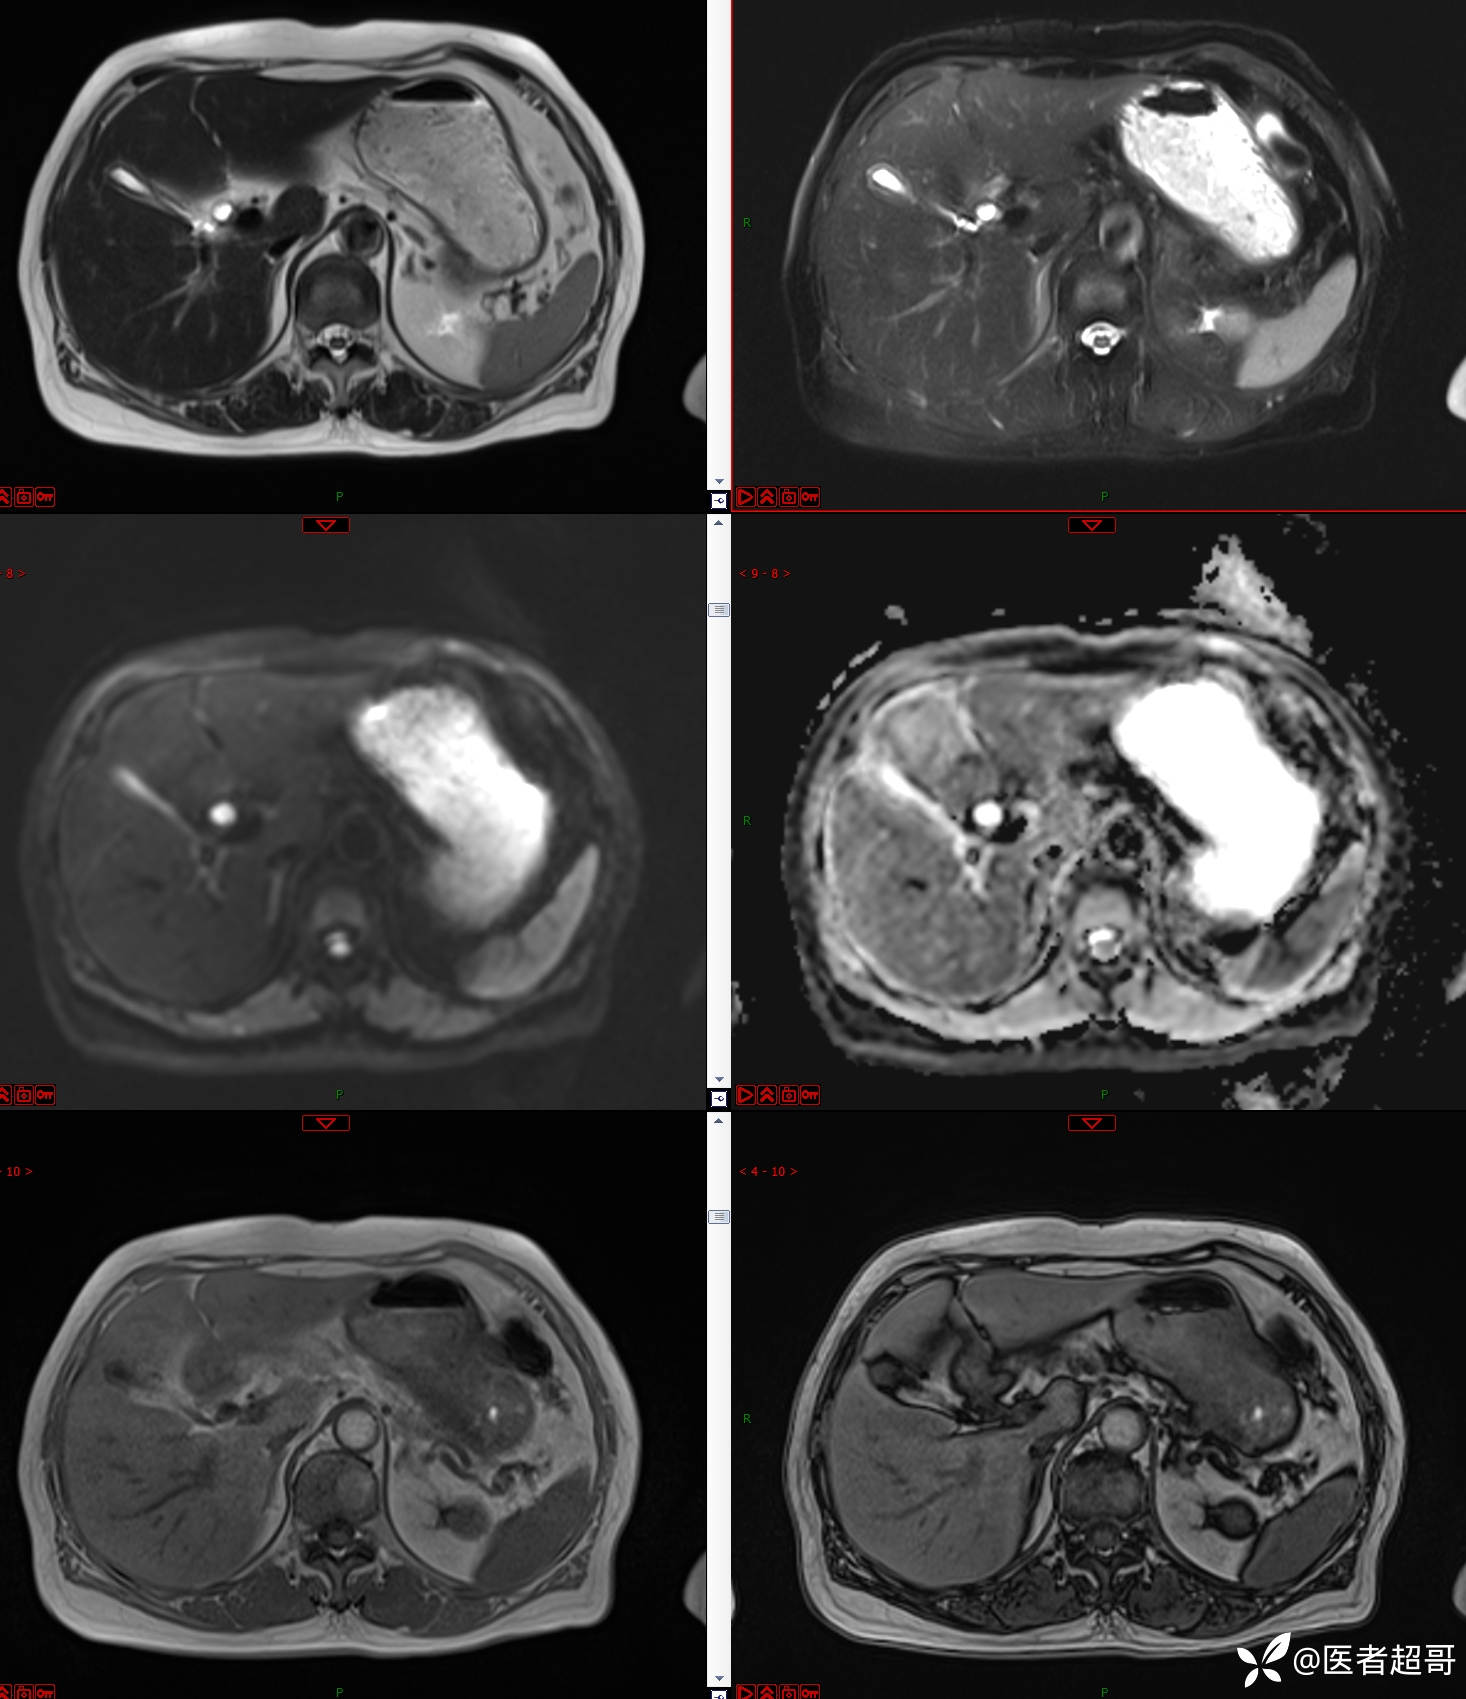

左肾占位2个月就诊,有病理,请分析!

患者 女 73岁

主 诉:查体发现左肾占位2月。

现病史:患者自述2月前于镇中心卫生院行腹部超声发现:左肾实性占位。患者无尿频尿急尿痛,无发热寒战,无恶心呕吐。未行特殊治疗。现患者为求进一步诊治,就诊我院,门诊以“肾肿物”为诊断收入院,患者自发病以来,神志清,精神可,饮食可,睡眠一般,大便正常,体重未见明显改变。